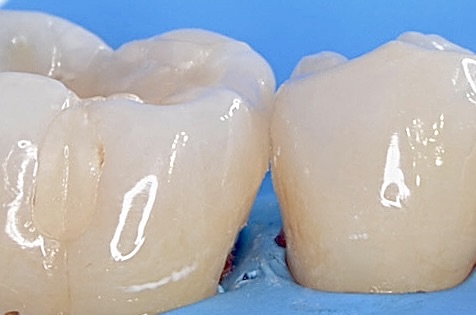

レジン充填

フロワブルレジンの表面張力を利用して、滑らかで継ぎ目のない修復ができました。 -

咬合面観